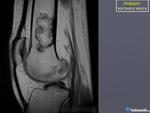

Женщина 1952 г.р.,направлена с диагнозом остеоартроз

Энхондрома, инфаркт кости, хондросаркома. Я в заключении такой бы диф. ряд написал.

На мой взгляд имеет место быть "Хрящевая матрица"

+1.Энхондорма? Хондросаркома?? Для уточнения рекомендована КТ коленного сустава.

Значит, что имеются элементы хрящевой ткани. Есть вероятность наличия хрящевой опухоли.

Большое спасибо за комментарии!Сегодня пациентка принесла архивные снимки обоих коленных суставов,за 2008,2009,2011 года -картина такая же и на тех снимках,а на снимках правого коленного сустава за 2008 год такой же участок(немного меньших размеров) в области метадиафиза большеберцовой кости.Ни МРТ ни КТ никогда не делала.

Энхондрома все же не исключается.

Инфаркт костного мозга.

На представленных рентгенограммах паттерн действительного не "инфарктный", но спорить можно долго, а правду узнаем только выполнив МРТ или РКТ.

Возможности КТ и МРТ в диагностике данного дифряда широко известны и как безвредный метод исследования можно рекомендовать МРТ нижней трети бедра.